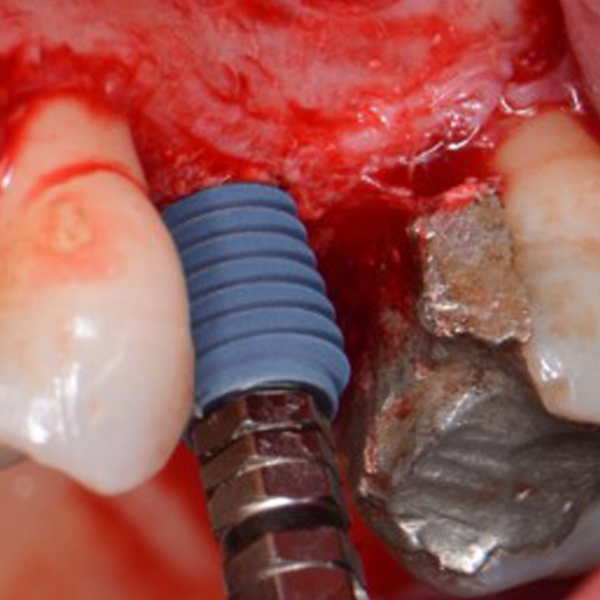

Removal Of Implant, Sinus Lift And Implant Replacement